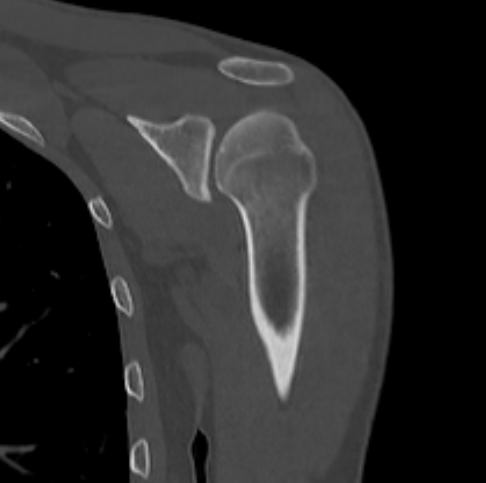

Мультиспиральная компьютерная томография является наилучшим методом диагностики патологии костной ткани и применяется для выявления различных патологических процессов в области плечевой кости.

Методика КТ построена на использовании ионизирующего излучения, которое в разной степени поглощается органами и тканями человека. Рентгеновские лучи лучше всего поглощаются костными структурами, поэтому на послойных изображениях, полученных при КТ-сканировании, хорошо видна плотность и внутреннее строение плечевой кости, а также плечевого и локтевого суставов. При этом визуализируются костные повреждения, очаги деструкции, воспалительные изменения.

Что показывает КТ плечевой кости

- повреждения костей в результате полученной травмы – трещины, переломы, смещения.